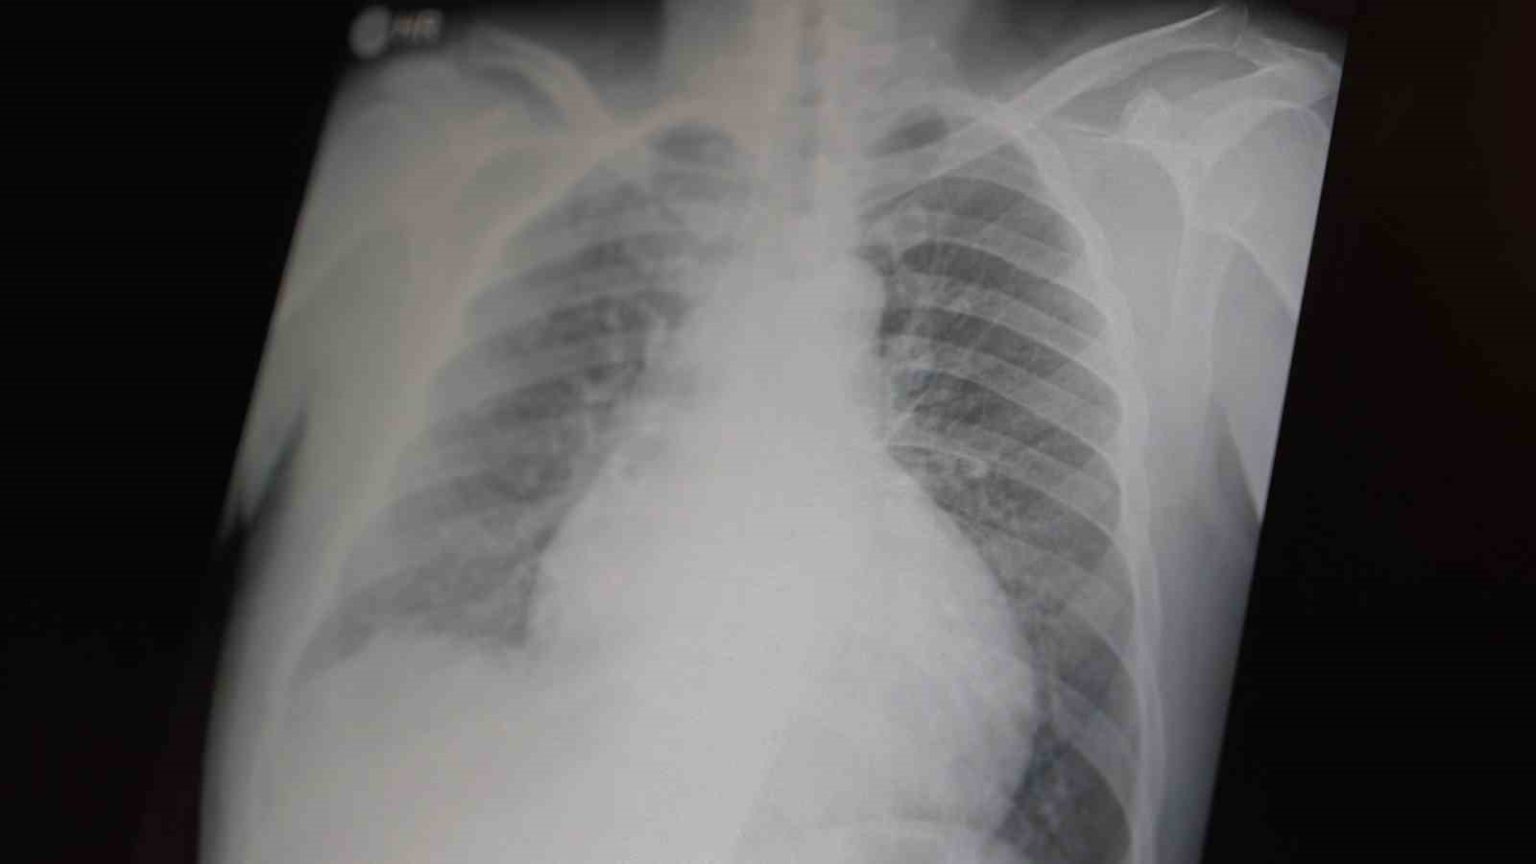

Prof. Dr. Şevket Özkaya, çocukları ve gençleri etkileyen bağımlılıklar hakkında açıklamalarda bulundu. Metamfetaminin sentetik bir uyuşturucu olduğunu ve kullanımının ölümcül sonuçlar doğurduğunu ifade eden Özkaya, “Tüm dünyada çocukları ve gençleri etkileyen iki önemli bağımlılıktan bahsetmek istiyorum. Bunlar metamfetamin ve kokain bağımlılığıdır. Metamfetamin en ölümcül, en çok bağımlılık yapan, okul çağında en kolay ulaşılabilen bir sentetik uyuşturucudur. Kullanıma bağlı ciddi akciğer ve karaciğer sorunları ortaya çıkıyor. Çok küçük dozlarda bile anında bağımlılık yapabiliyor ve tedaviyle bırakılması çok zor bir bağımlılıktır” dedi.

Açıklamalarında, her iki uyuşturucunun beyin hasarı oluşturduğunu ve nöro sinir hücrelerini harap ederek solunum ve kalbin durmasına sebep olduğunu vurgulayan Özkaya, “Metamfetamin tüm dünyada bir sorun olmanın ötesinde, ülkemizde de gençlerimizi etkileyen toplumsal bir sorun olarak görülmelidir” ifadelerini kullandı.